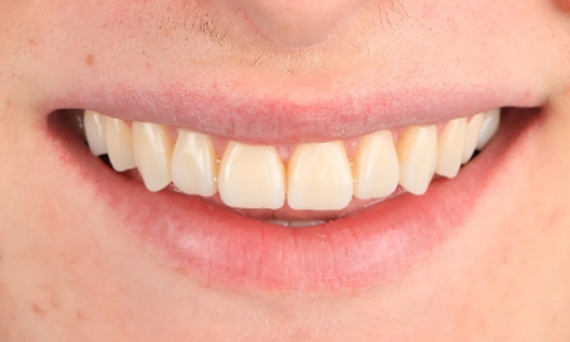

Facettes à préparation minimale après un traumatisme des incisives centrales maxillaires

Restauration avec un matériau hautement esthétique en un jour après un traumatisme des incisives centrales maxillaires.

Avant : Situation clinique préopératoire. Traumatisme des incisives centrales maxillaires

Après : Restaurations collées.

Dr. Mohamed Hassanien

Le Caire, Egypte